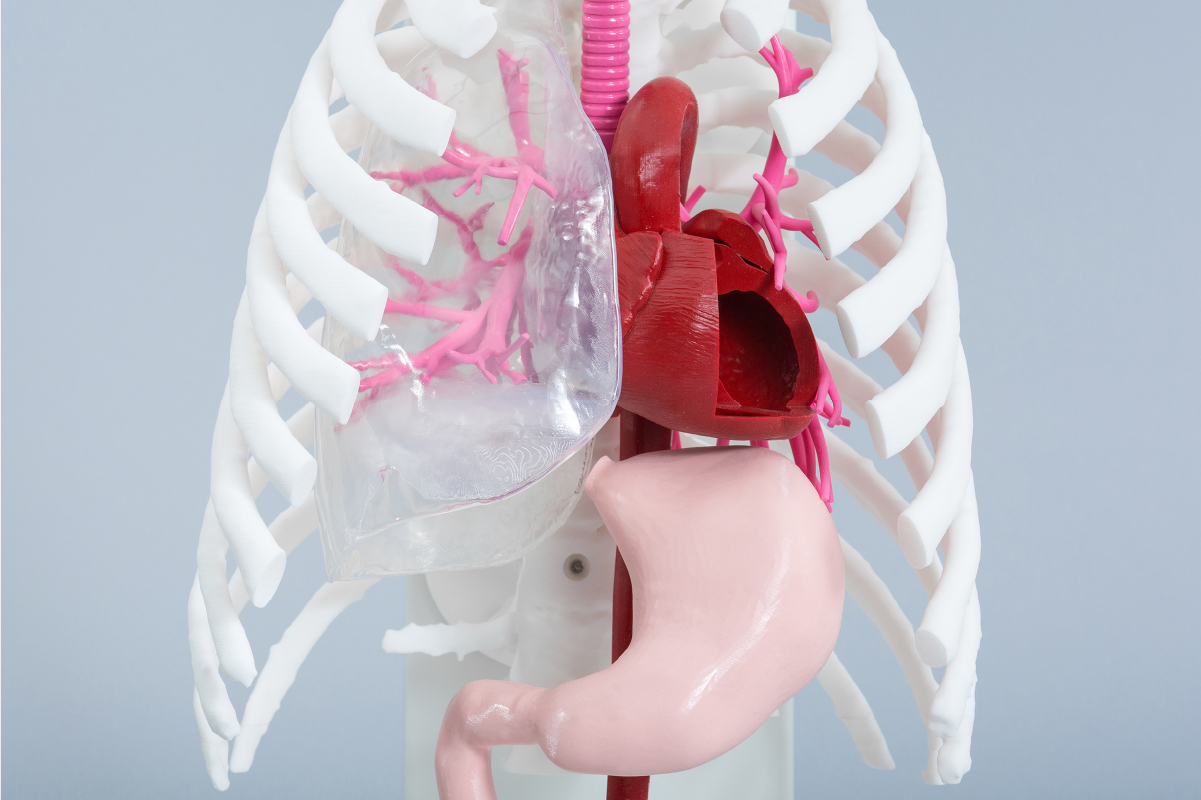

JMC's medical model fabrication service uses 3D printers and other digital technologies to achieve a high degree of freedom in model fabrication. 3D printed resin models are combined with vacuum casting technology to transfer the shape onto transparent, soft, and other materials. By combining 3D printed resin models with vacuum casting technology, we are able to transfer shapes onto transparent, soft, and other materials, providing services that thoroughly pursue the shapes, textures, and functions that customers demand.

In general, soft models often fail to reproduce some shapes, such as simplifying the inside of organs, but JMC Lab possesses a unique technology that combines 3D printing and casting technologies to faithfully reproduce the outside and inside of organs. JMC Lab has a unique technology that combines 3D printing and casting techniques to faithfully reproduce the outside and inside of organs. This method allows for a higher degree of material flexibility than direct 3D printing of soft materials, and allows for adjustments in hardness, color, X-ray transmission, etc.

We have a system in place that allows us to work 24 hours a day, 7 days a week on rigid models that are output directly from the 3D printer, so that we can deliver them quickly to our customers in fields that require speed, such as preoperative simulation and prototyping of medical devices. We have a variety of output methods, including optical, SLS, and inkjet, so you can choose the most suitable method for your application.

JMC all of our models are made to order. In addition to directly sculpting the customer's 3D data, we can also customize the data and create data from CT and MRI. Even if you do not have any original data, we can make a proposal to realize your image based on your sketch.

DICOM, which stands for Digital Imaging and COmmunication in Medicine, is the name of a global standard used for the storage and communication of medical images. DICOM was originally developed by the American College of Radiology (ACR) and the North American Electronics Manufacturers Association (NEMA) in 1985, and was renamed DICOM in 1993. In 1993, the name was changed to DICOM, and it came to be used as a standard. In Japan, it was officially recognized as a standard by the former Ministry of Health and Welfare in 1999. JMC can produce high-precision medical models by using DICOM data captured by CT scans and MRIs. Depending on the target area, a model with high reproducibility can be produced if slice images with a pitch of 1 to 2 mm are provided.

JMC uses a software called "mimics" to construct precise skeletal and organ shapes from DICOM data. JMC

uses mimics software to construct precise shapes of skeletons and organs from DICOM data. By having

specialized engineers perform image processing using mimics, it is possible to extract only the areas of

interest and output higher quality 3D data with less distortion caused by metal products such as gold

teeth and pacemakers.